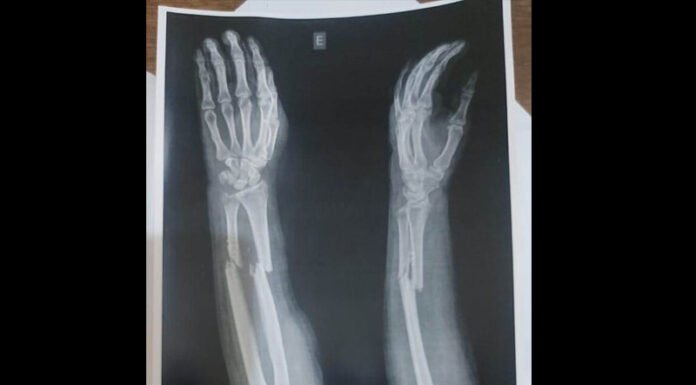

A paciente Marinês Luciano sofreu um acidente de moto no dia 26 de junho, ocasião em que quebrou o braço esquerdo. No Hospital Geral de Roraima (HGR) ela foi informada que precisaria passar por uma cirurgia, no entanto, está há quase dois meses tentando marcar o procedimento.

“Fui orientada a procurar a ortopedia do...